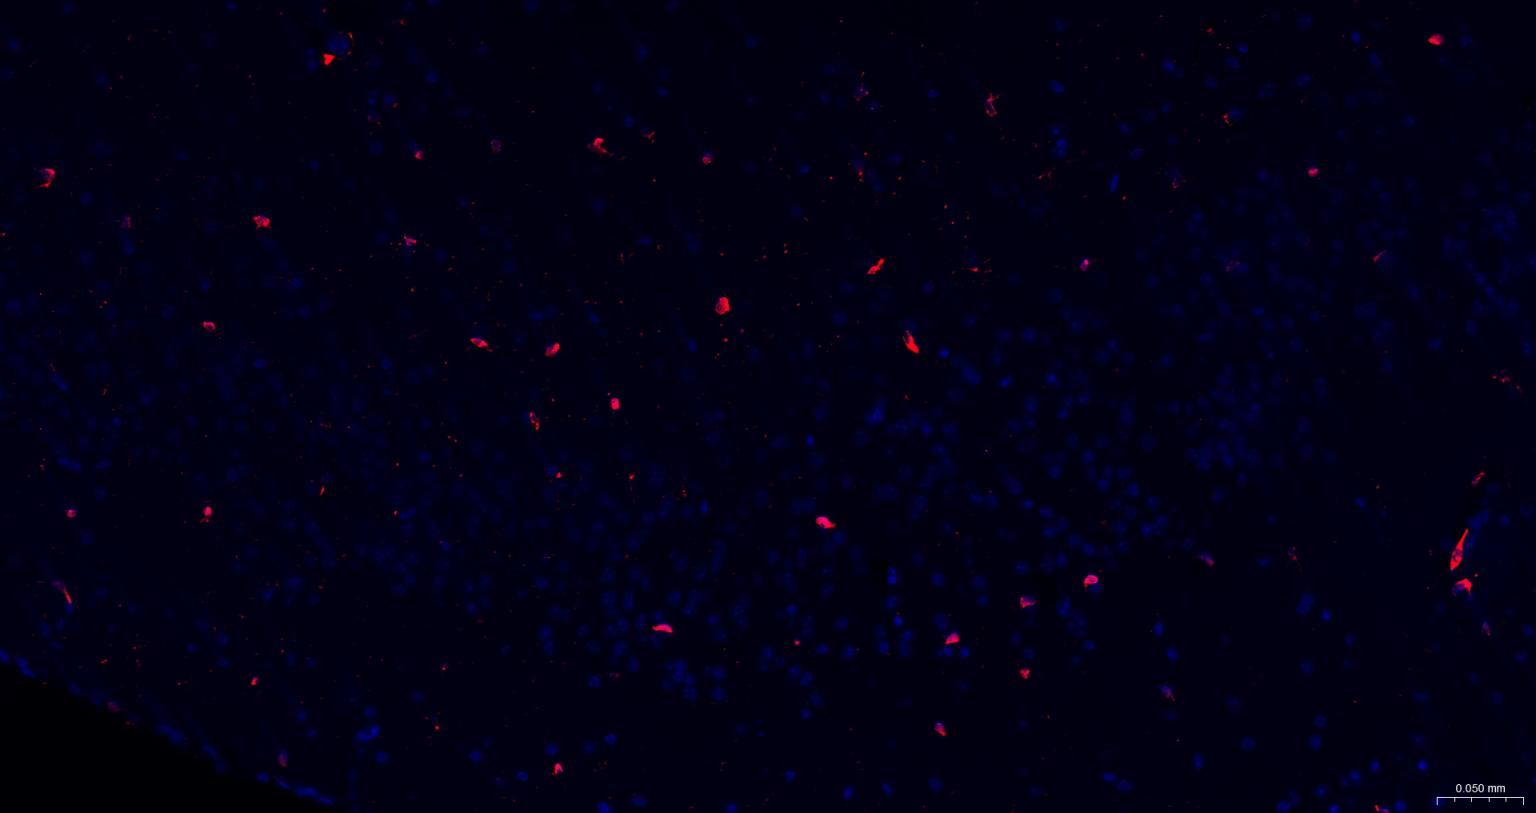

Paraformaldehyde-fixed, paraffin embedded Rat Cerebrum; Antigen retrieval by boiling in sodium citrate buffer (pH6.0) for 15 min; The section was incubated with AIF1 / Iba1 Polyclonal Antibody, Unconjugated (bs-1363R) at 1:200 overnight at 4°C. Followed by conjugated Goat Anti-Rabbit IgG antibody (Red, bs-0295G-BF594), DAPI (blue, C02-04002) was used to stain the cell nuclei.